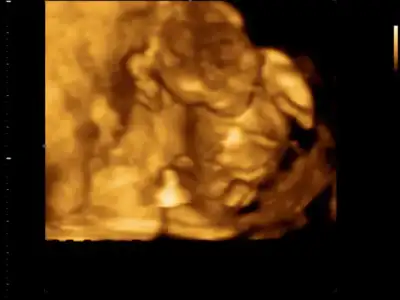

Dün sonunda doktora gittik, Fakat heyecanlı bekleyiş sona ermedi :) Velet çok hareketliydi eller kollar durmuyordu. Gel gelelim ki bacak bacak üstüne atmış, makas yapmış resmen :) Bir türlü açtıramadık :) öğrenemedik yani cinsiyetini... Bakalım üçlü testte öğreniriz inşallah... Resmini ekliyorum bakın bakalım bebişime :)

bu arada benim renkli ultrason görüntüsünü ekliyim ya ne salağım ekleyemedimdi şimdiye.

bu arada benim renkli ultrason görüntüsünü ekliyim ya ne salağım ekleyemedimdi şimdiye.

ayfer.o gorunen sey pipisi mi?gobek kordonu sag tarafta bellı zaten ama onla mı karıstırdım kı.

bu arada benim renkli ultrason görüntüsünü ekliyim ya ne salağım ekleyemedimdi şimdiye.

bu arada benim renkli ultrason görüntüsünü ekliyim ya ne salağım ekleyemedimdi şimdiye.

Maşallah bebişine. Bu kontrole gittiğimizde doktorumuza desekde daha fazla çekse bebişi. Seyretmeye doyamıyoruz.

ayfer.o gorunen sey pipisi mi?gobek kordonu sag tarafta bellı zaten ama onla mı karıstırdım kı.

şaka bir yana pipi orada fotoda çok belirgin değil canım göbek bağı uzun şu anda ve birkaç yerde görünüyor.üstteki kolu imiş zaten.bende sordumdu doktora.